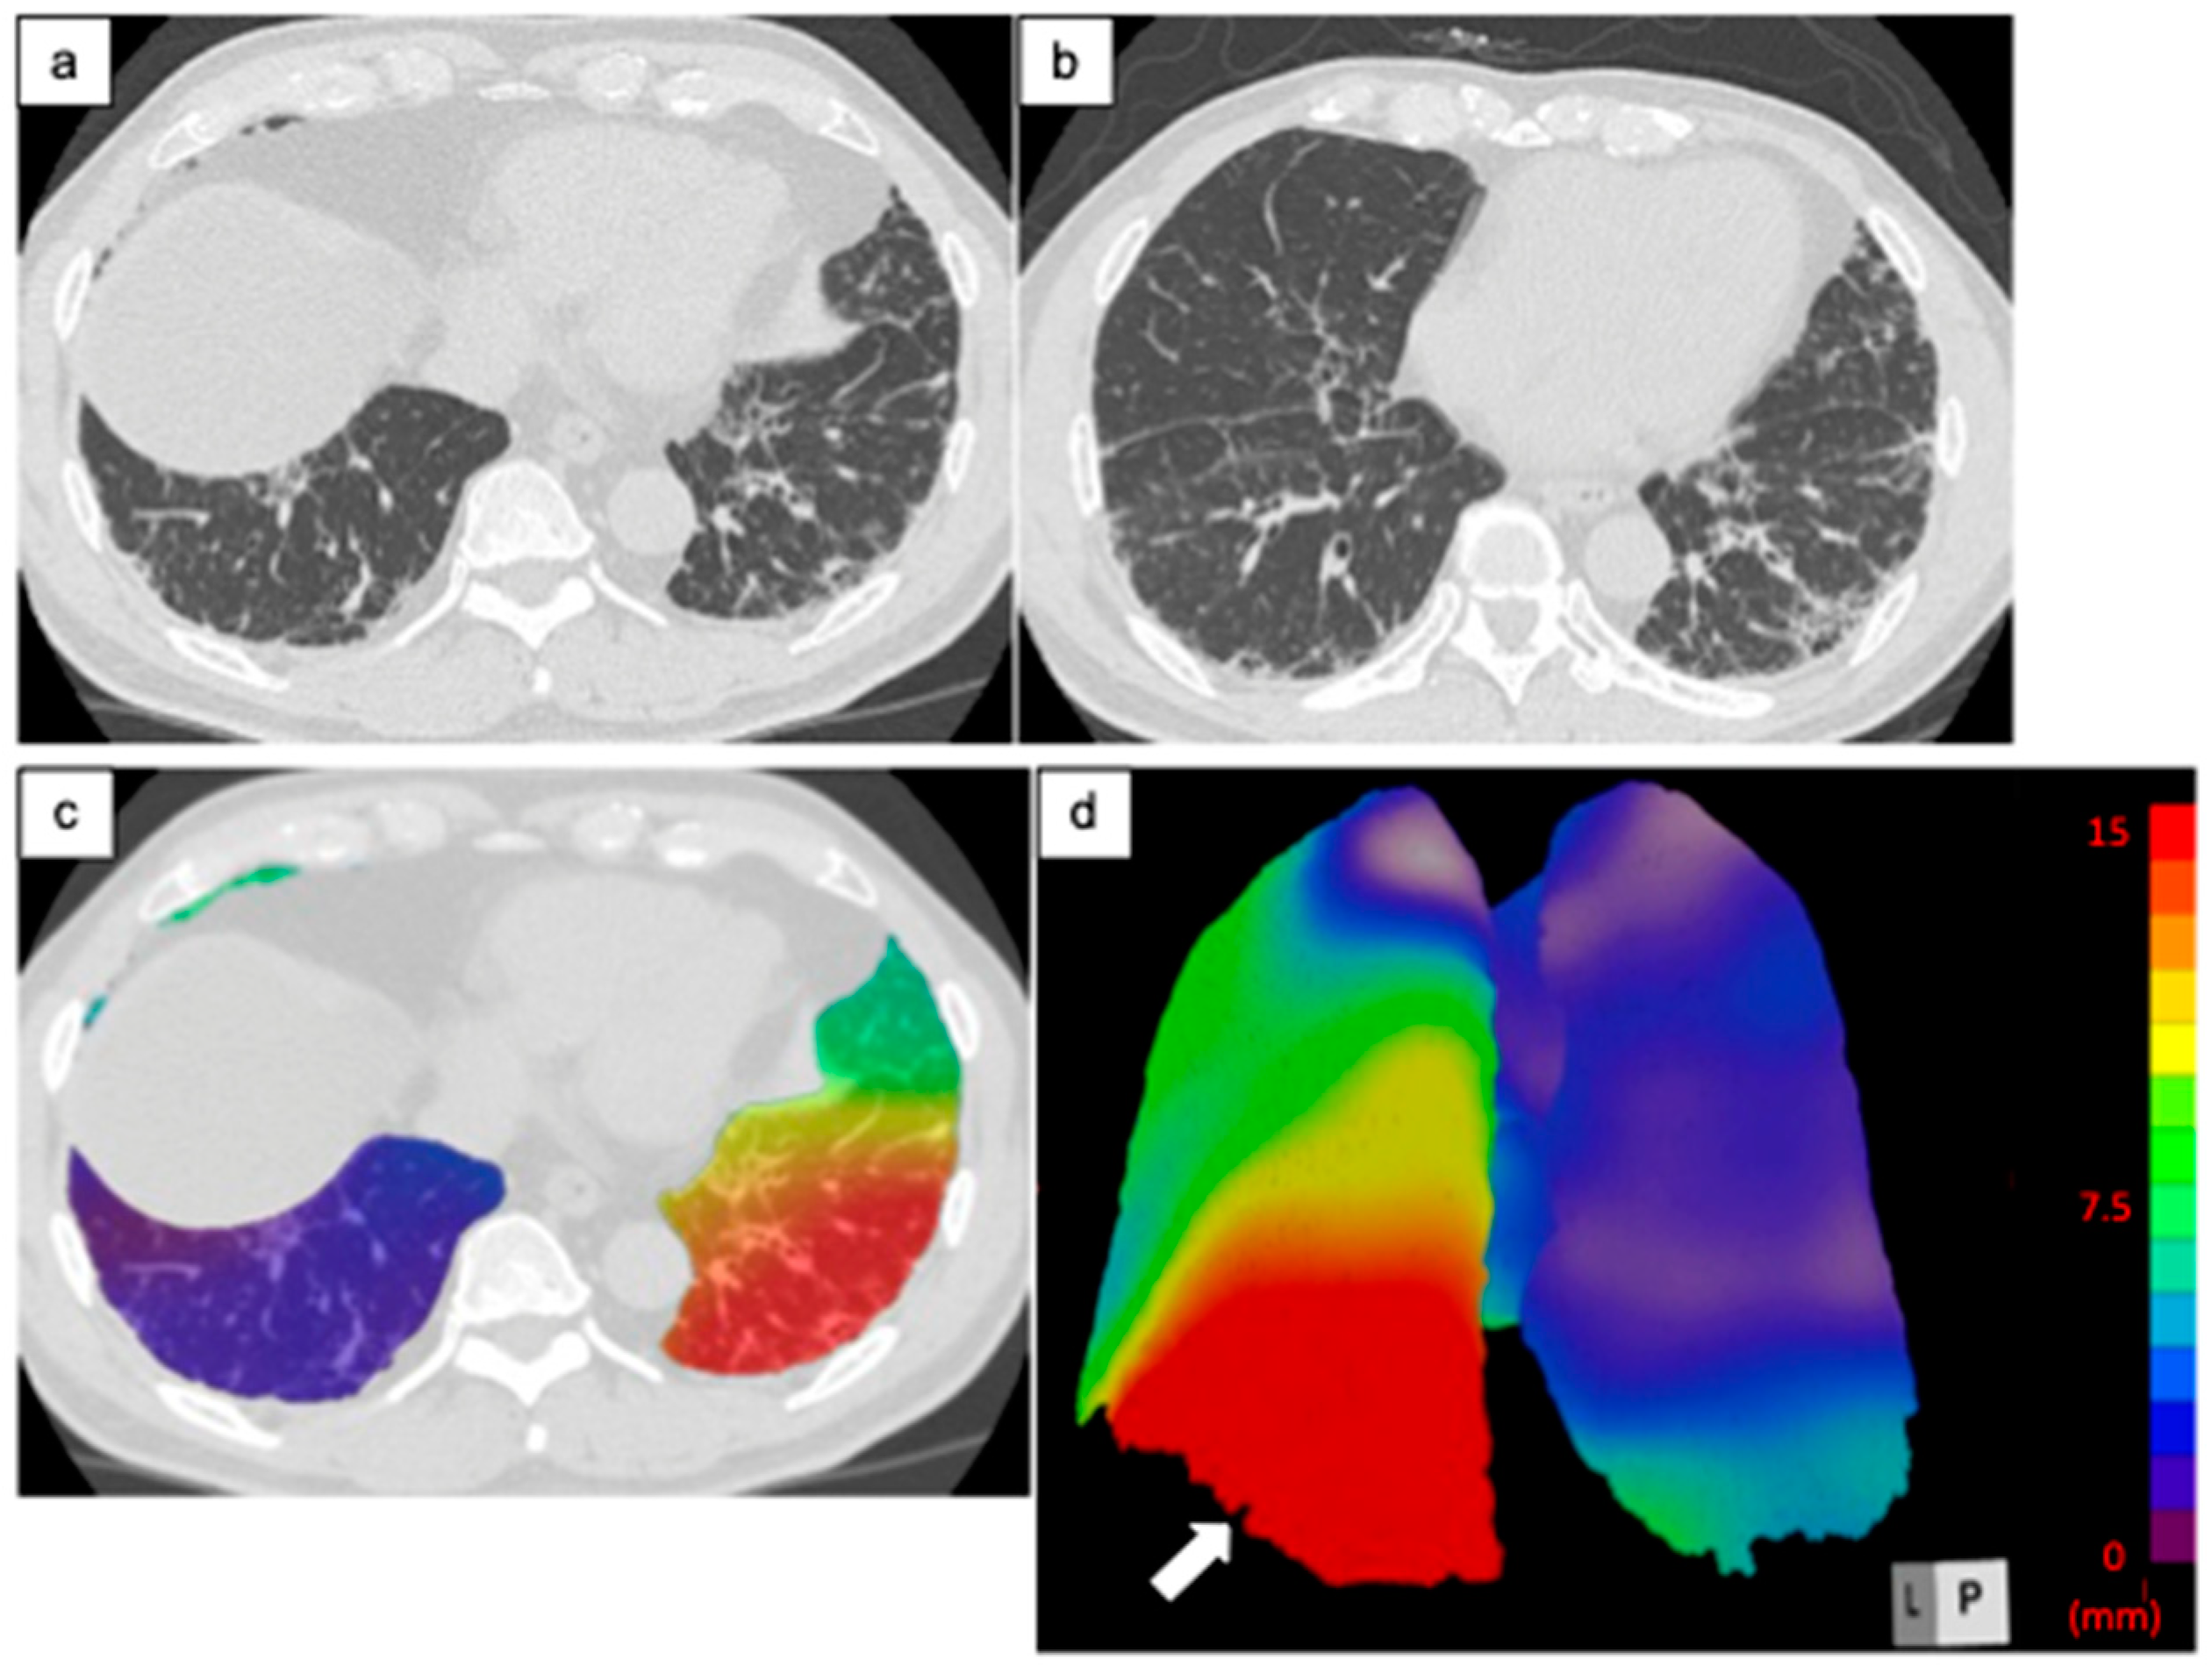

Figure 4.

Computed tomography (CT) images of a 68-year-old man with idiopathic pulmonary fibrosis and three-dimensional average displacement (3D-AD) color maps. (a) Initial CT image shows subpleural reticulation in the lung base. (b) Follow-up CT image after one year shows an increase in subpleural reticulations predominantly in the posterior areas of the left lung base. (c,d) Color map of the 3D-AD shows a greater deviation (red in the color map) in the posterior areas of the left lung base (white arrow), corresponding to the original CT images. In this case, 3D-AD in the whole lung/lower lobe of the left lung = 5.9 mm/14 mm.